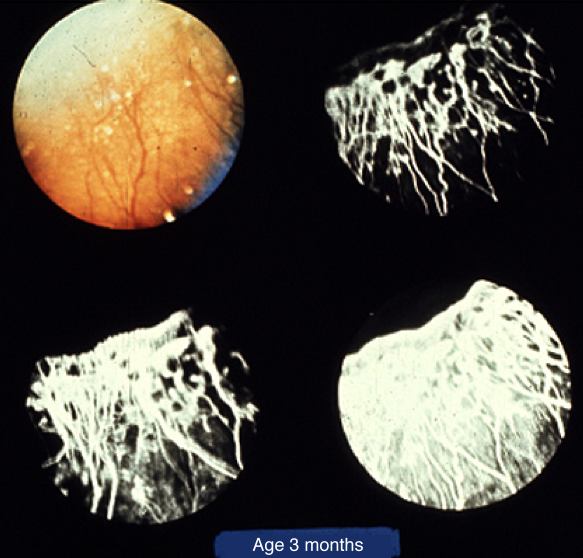

Figure 14. Digital fluorescein angiogram of ROP

Fundus photograph (top left) and series of images from a fluorescein angiogram of an ROP subject with stage 3 ROP.